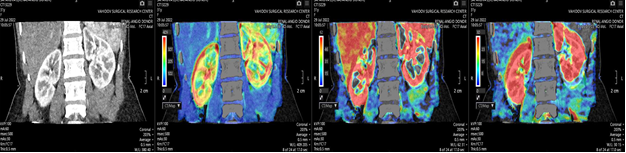

Renal perfusion measurement included AF, Equi BV, and FE. ROIs were placed in the cortical layer of upper, middle, and lower kidney segments (frontal planes) as well as anterior, lateral, and posterior segments (axial planes). This allowed for averaging across different parenchymal zones. Mean values and standard deviations were calculated for each parameter.Perfusion maps were also used to analyze renal cortical blood flow, blood volume, and vascular wall permeability. Perfusion indices were measured in both kidneys, enabling comparison between kidneys with different anatomical features. Representative perfusion maps are shown in Fig. 2. | Figure 2. Renal perfusion maps |